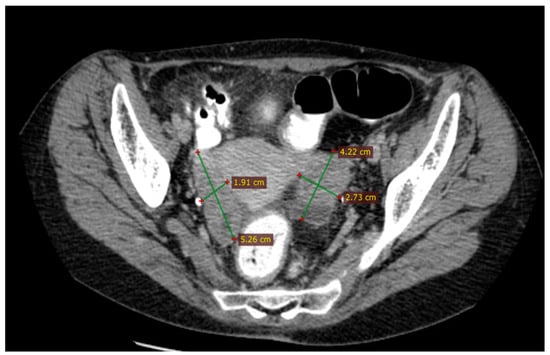

2.2.3. Examinations and Investigations